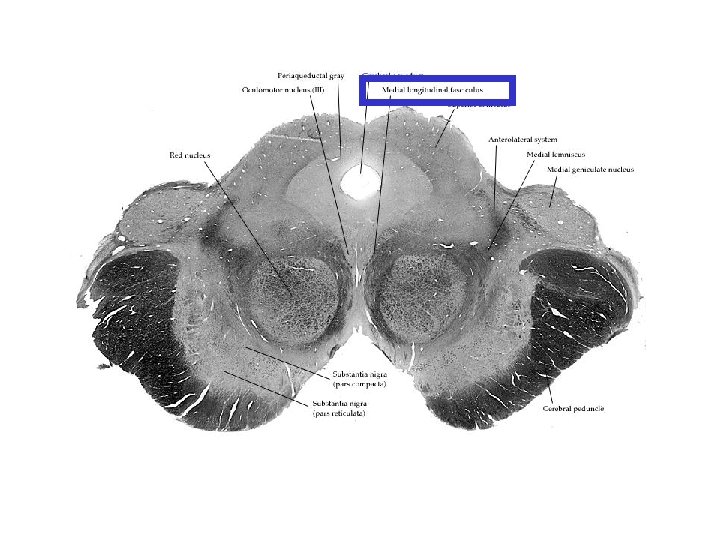

Fasciculus longitudinalis medialis Orta çizgiye çok yakın olarak yer alır. Kafa çiftlerinin birbirleri ile olan bağlantısını sağlar Beyin sapında göz kaslarını inerve eden çekirdekler arasında ve bu çekirdekler ile vestibular sistem arasında önemli rol oynar.